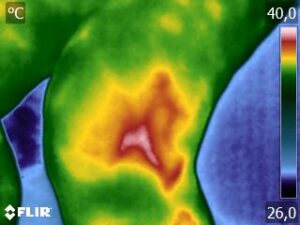

Como no caso da sequência de termogramas abaixo de uma paciente do sexo feminino, 42 anos, sem comorbidade e que apresentou dor em joelhos após treino de musculação. Foi realizado uma Análise Termofuncional e detectado alterações térmicas condizentes com o relato de dor.

Estas informações foram a oportunidade para convencer a paciente a realizar uma ressonância magnética para determinar o grau de comprometimento tecidual. Pois sem isso, após a melhora da dor, a liberação de carga e até a carga terapêutica ficariam limitadas.

Já com este conhecimento foi possível determinar um tratamento que abarcasse as áreas de dor e as áreas de comprometimento tecidual que apresentam inflamação, até a paciente retornar com o resultado da ressonância.

Isso adianta e muito a reabilitação, pois oferece informação que a olho nu não seria possível.